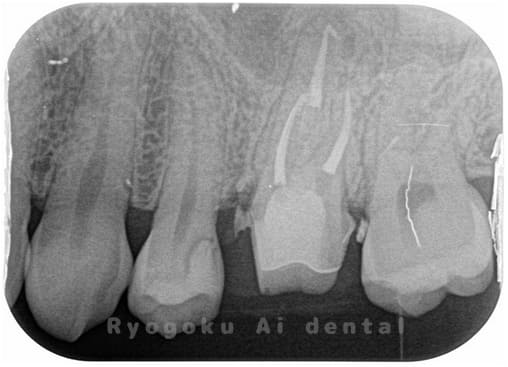

Case07

-

- 原因

- 慢性根尖性歯周炎(16・17・15部)

- 治療内容

- マイクロエンド(3歯分)

- 治療費用

- 308,000円(3歯分)※被せ物を除く

右上の違和感が取れないとのことで来院された患者さんです。ファイルという器具が歯の根の中で折れていることを説明し、マイクロスコープを使用した根管治療を提案し、治療を行いました。折れたファイルも取り除くことができ、現在の経過は良好です。

<リスク・副作用>

術後は痛み、腫れ、痺れなどの副作用が生じる場合があります。症状が再発する可能性があります。